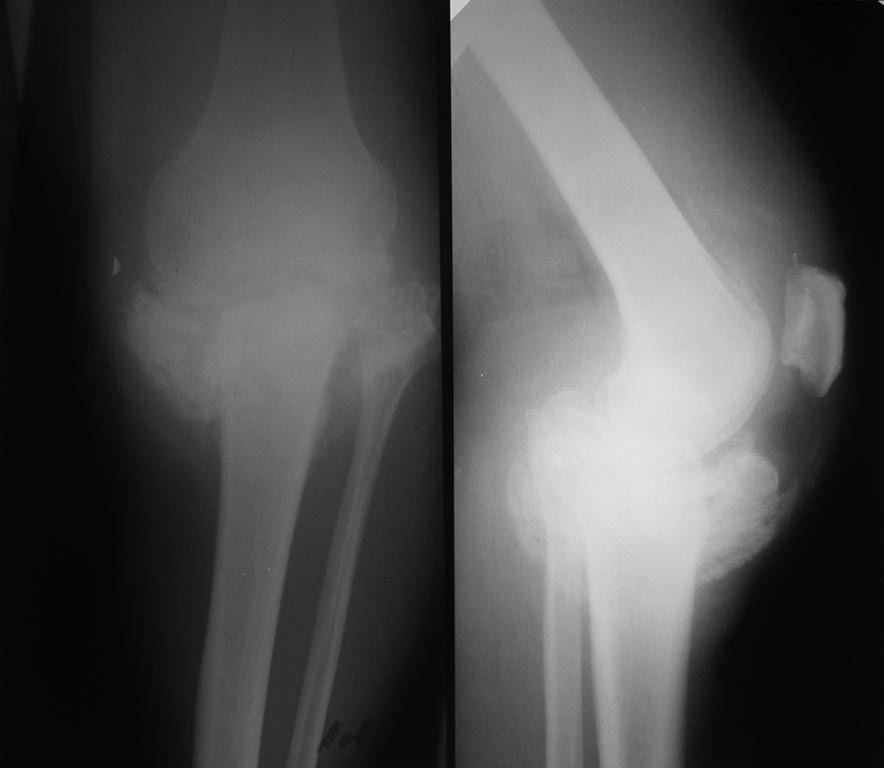

Пациент мужчина, 46 лет, гражданин Украины, рост 170, вес около 70-74. Работал до травмы и в настоящее время, средние физические нагрузки. Травма в декабре 2014, со слов выставил прямую ногу вперед во время катания на велосипеде, факту травмы не придал значение вплоть до моего осмотра (апрель 2015), лечил ушиб. Рентгенограммы (1) январь 2015 год, (2) 25.05.2015 г.

Диагноз: Застарелый многооскольчатый (С3) перелом проксимального отдела ББК. По срокам после травмы (более 6 мес): Ложный сустав (неоартроз) проксимального отдела ББК.